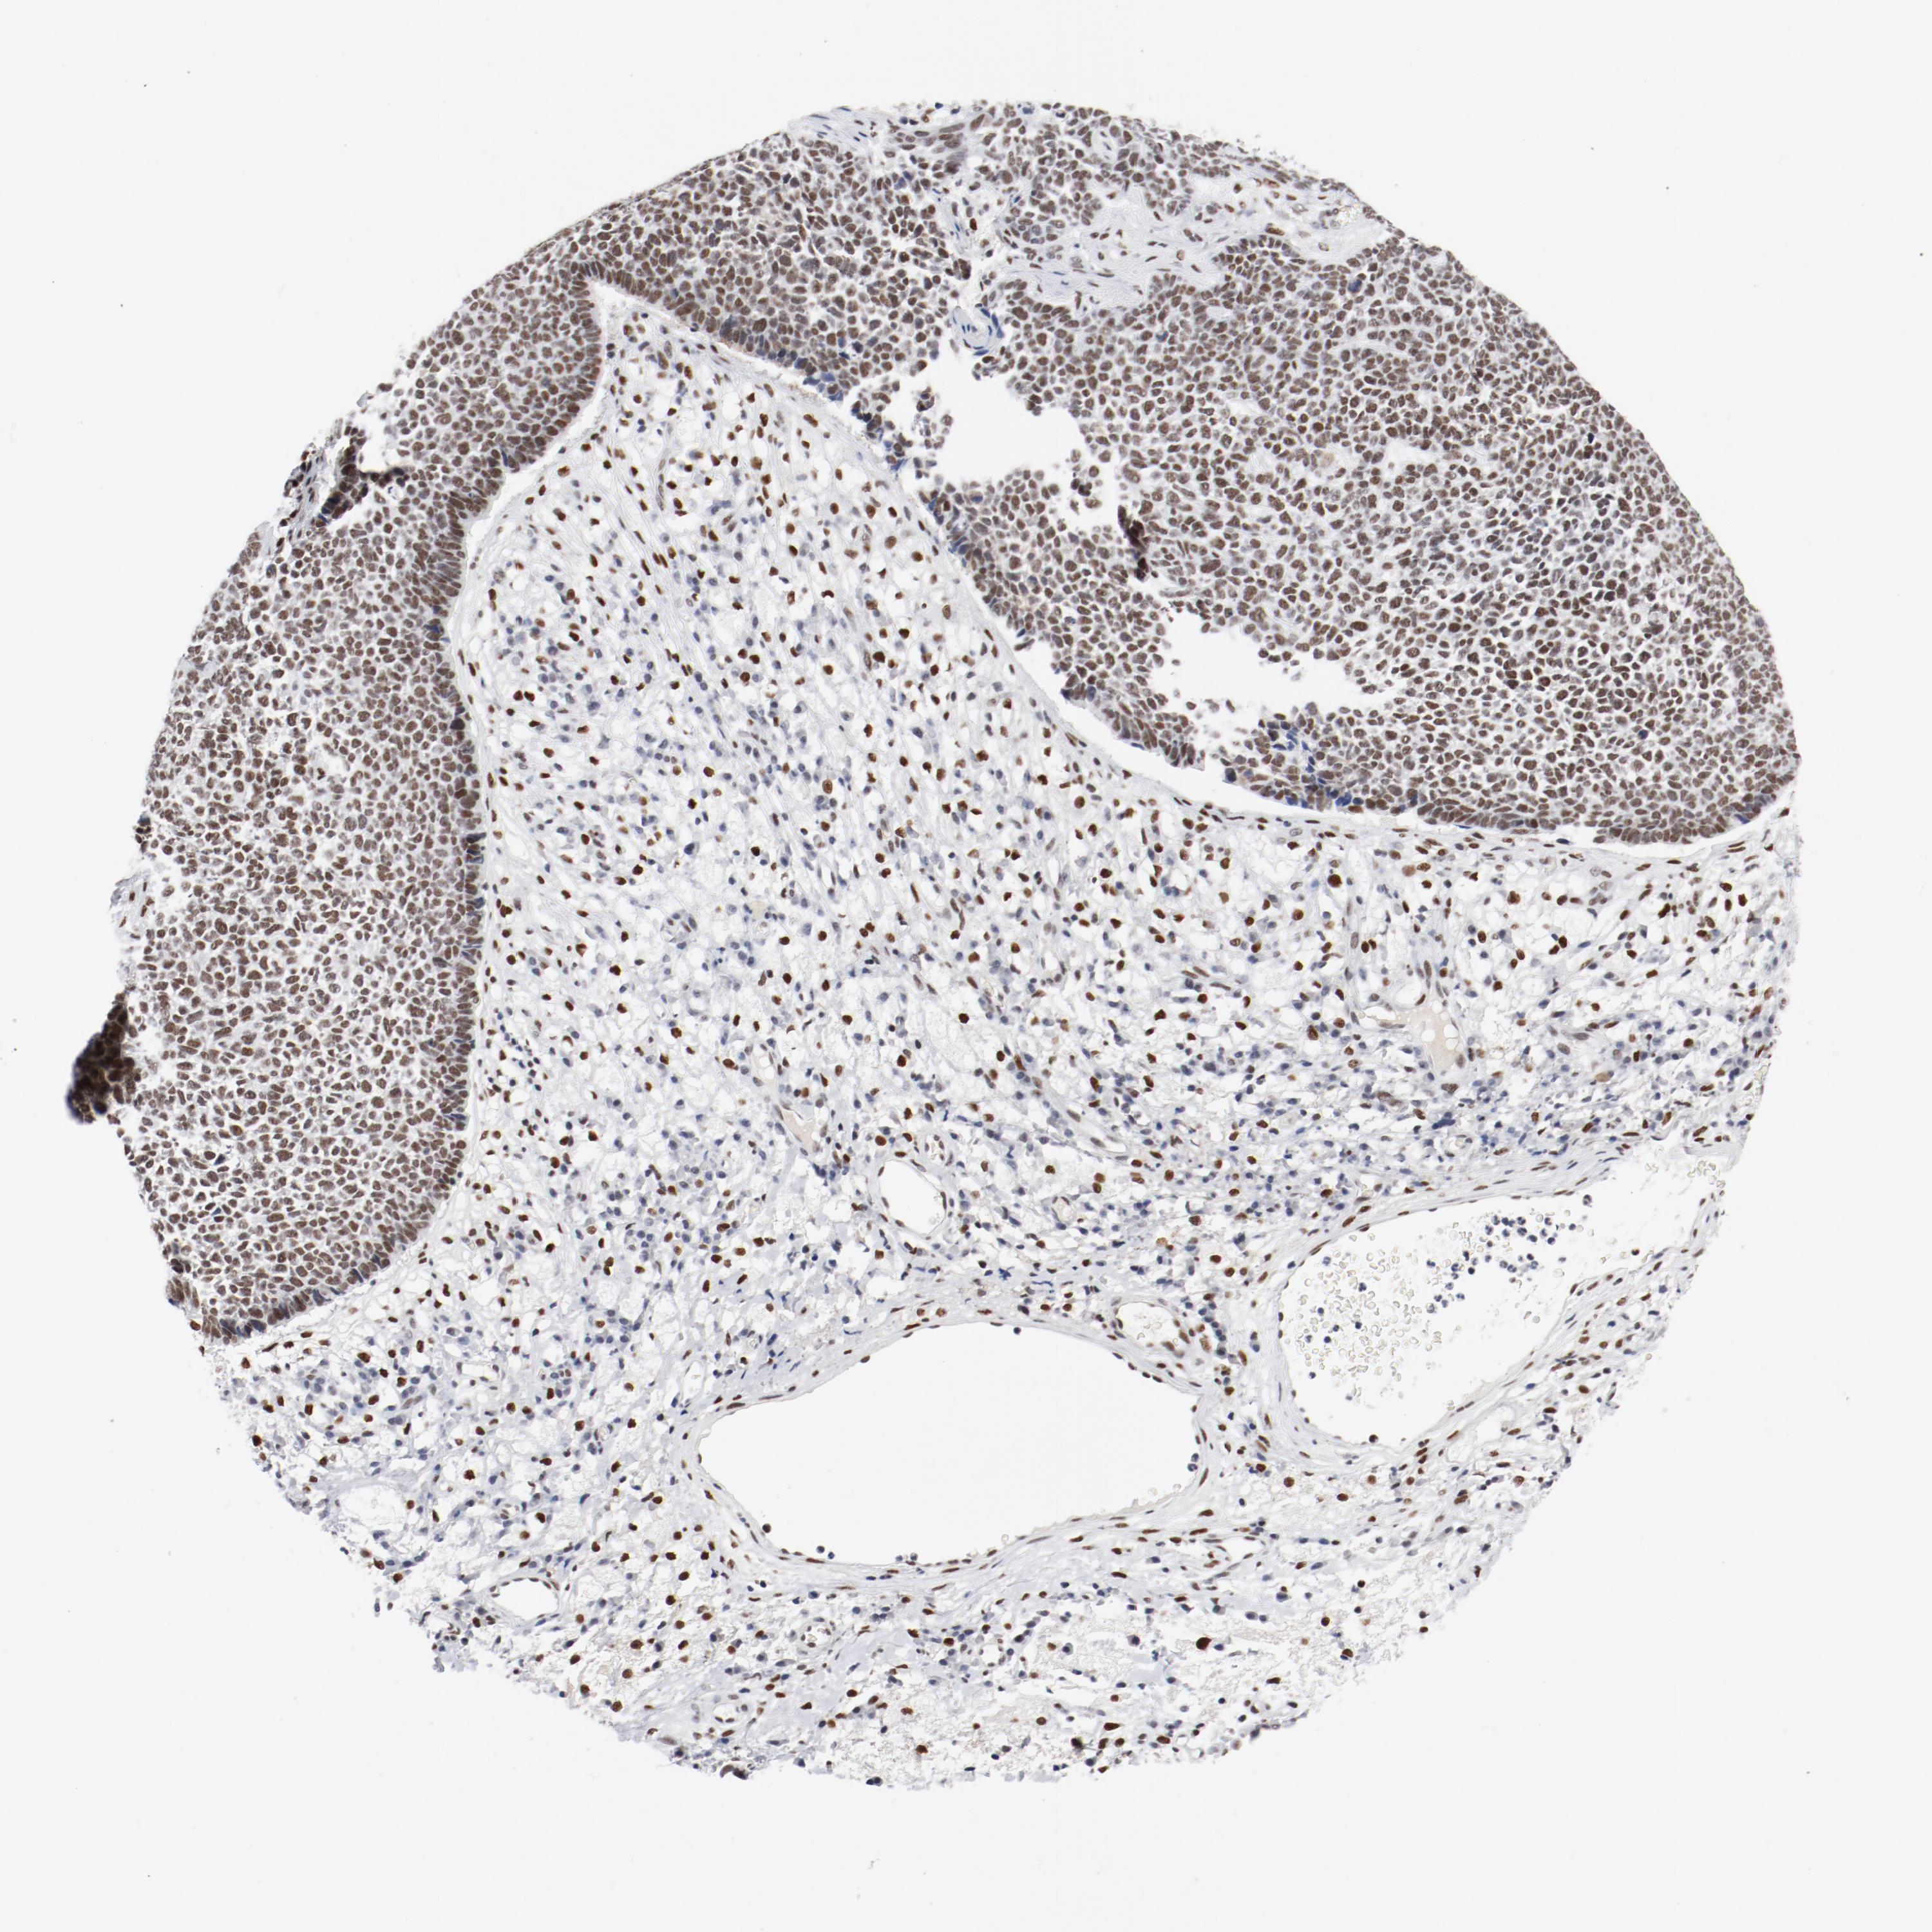

SKIN CANCER - Protein expressioni

A mouse-over function shows sample information and annotation data. Click on an image to view it in a full screen mode. Samples can be filtered based on level of antibody staining by selecting one or several of the following categories: high, medium, low and not detected. The assay and annotation is described here.

Antibody stainingi

Antibody staining in the annotated cell types in the current human tissue is reported as not detected, low, medium, or high, based on conventional immunohistochemistry profiling in selected tissues. This score is based on the combination of the staining intensity and fraction of stained cells.

Each image is clickable and will lead to virtual microscopy that enables deeper exploration of all samples and also displays staining intensity scores, fraction scores and subcellular localization as well as patient and tissue information for each sample.

Antibody HPA001759

Squamous cell carcinoma, NOS

Basal cell carcinoma